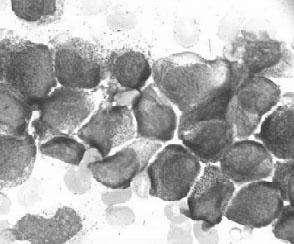

(3)急性颗粒增多的早幼粒细胞白血病(M3):骨髓中以颗粒增多的异常早幼粒细胞增生为主>30%(非红系细胞),其胞核大小不一,胞质中有大小不等的颗粒(见图3—7)。分为以下两种亚型:

图3—7 AML—M3骨髓象

1)M3a(粗颗粒型):嗜苯胺蓝颗粒粗大,密集甚或融合。

2)M3b(细颗粒型):嗜苯胺蓝颗粒密集而细小。